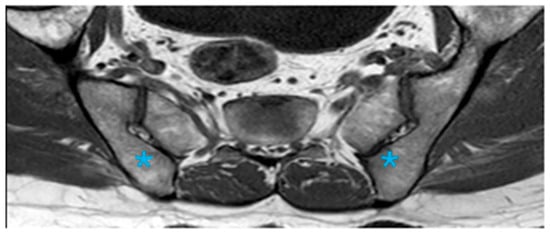

Assessment of Anatomical Variations in the Sacroiliac Joint Using Magnetic Resonance Imaging: A Retrospective Study of 840 Patients

Background/Objectives: This study aimed to examine the prevalence of anatomical variations in the sacroiliac joints (SIJs) as observed through Magnetic Resonance Imaging (MRI), to characterize their manifestations, and to identify MRI features that may resemble inflammatory alterations. Methods: A retrospective review was conducted on consecutive MRI scans of the SIJ performed from January 2009 to January 2022. Eight anatomical variations, along with associated edematous and structural changes, were assessed. Results: The study encompassed 840 patients, with anatomical variations identified in 39.7% of the cohort, occurring more frequently among female participants. The most prevalent variations were accessory SIJ (36.2%) and the iliosacral complex (32.2%). Notably, isolated synostosis and persistent ossification center variations were absent. The increased frequency of variations in women, as well as their correlation with advancing age, was statistically significant (p = 0.034). Accessory SIJ and dysmorphic alterations were linked to bone marrow edema and structural modifications. In the iliosacral complex and semicircular defect variations, prominent vascular structures were observed extending along the bone surfaces. The number and depth of edema slices in sacroiliitis exceeded those observed in the variation (p < 0.001). Conclusions: Anatomical variations of the SIJ are prevalent among women and tend to increase with advancing age. Given that these variations, particularly accessory SIJ and dysmorphic alterations, may present with edematous and structural signal intensity changes that resemble sacroiliitis, it is crucial to recognize these variations. It is recommended to assess axial and coronal images concurrently and to exercise caution in the interpretation of SIJ MR images. Full article

Show Figures

Figure 1